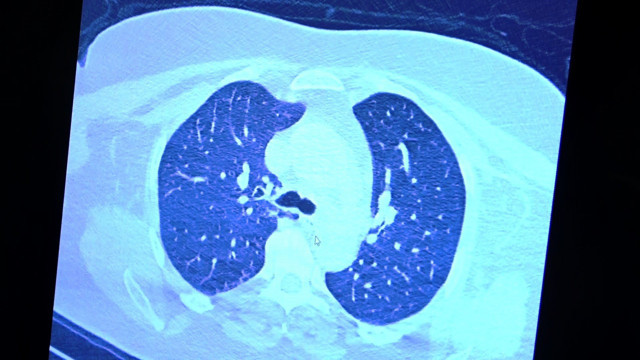

VM Medical Park Samsun Hastanesi’nde görev yapan Göğüs Hastalıkları Kliniği’nden Prof. Dr. Şevket Özkaya da bir hafta ilaç kullanmayan bir pozitif hastanın akciğer tomografisini inceledi. Hasta pozitif haldeyken ilk akciğer tomografisine bakıldı. Tomografide akciğerlerdeki tutulmanın az olduğu gözlemlendi. Akabinde aynı hastanın verilen ilaçları kullanmamış ve 1 hafta boyunca tedaviye uymamış haldeki akciğer tomografisine bakıldı. Sonuç ise ilaç kullanımının önemini ortaya çıkardı. Hastanın akciğer tomografisinde yaygın buzlu camların ve hava yollarının hava yerine ciddi şekilde sıvı ile dolduğu gözlemlendi.

Akciğer tomografisinde oluşan değişim ile ilgili bilgi veren Prof. Dr. Şevket Özkaya, "Ekranda 55 yaşında bir kadın hastamızın filmini görüyorsunuz. Bu kadın hastamız acil servisimize ateş şikâyetiyle geldi ve korona virüsünden şüphe ettik. Testini yaptığımızda ise testin sonucu pozitif geldi. Tomografi çektiğimiz zaman akciğerlerinde henüz ciddi bir tutulum görünmezken hastamız 55 yaşında olduğu için her an ilerleyebilir korkusuyla Sağlık Bakanlığımızın önerdiği ilaçları ve reçeteyi hastanemizden kendisine verdik. Hasta kendini evde karantinaya aldı fakat sonradan öğrendik ki tereddüt ettiği için ilaçlarını kullanmayarak kendini evde tedavisiz bırakmış. Yaklaşık bir hafta sonra aynı hasta acil servisimize bu sefer solunum yetmezliği şikâyetiyle geldi. Solunum yetmezliği gelişince hastanın akciğer tomografisinde ‘buzlu cam’ dediğimiz ve daha ileri konsolide alanların oluştuğunu gördük. Yaygın akciğer harabiyeti dediğimiz bir tablo oluşmuştu. Bu durumda hastada solunum yetmezliği olduğu için yoğun bakıma almak zorunda kaldık" dedi.